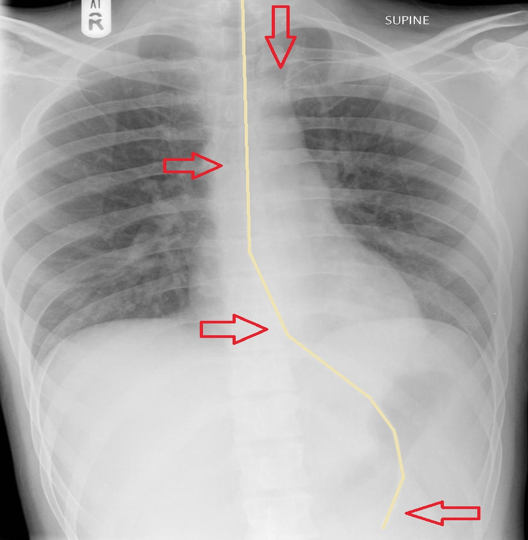

What is this AP CXR showing?

Left Lower Lobe collapse –> Sail sign

Loss of silouette sign of left demidiaphragm and descending aorta

Inferior displacement of left hilum

Inferior displacement of oblique fissue